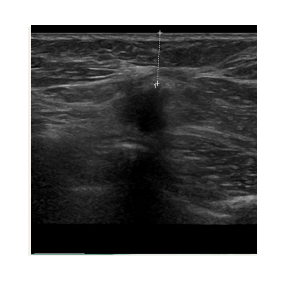

The freezing is achieved with liquid nitrogen  which flows through a probe (needle.) The needle is inserted into the tumor under ultrasound guidance. This allows us to position it very precisely, ensuring that the tumor is at the centre of the freezing zone.

This creates a large ball of ice that engulfs the tumor. By alternating freeze and thaw cycles, the cells in the tumor are destroyed. By the end of the procedure there should be no viable cancer cells left. The progress of ice ball development is closely monitored throughout the procedure to ensure safety.

Using ultrasound guidance, a visica cryoprobe is positioned in the center of the lesion

The cycle is activated and an iceball forms around the tumor. The freezing temperatures destroy the tumor tissue

Freeze and thaw cycles are used sequentially to destroy the tumour